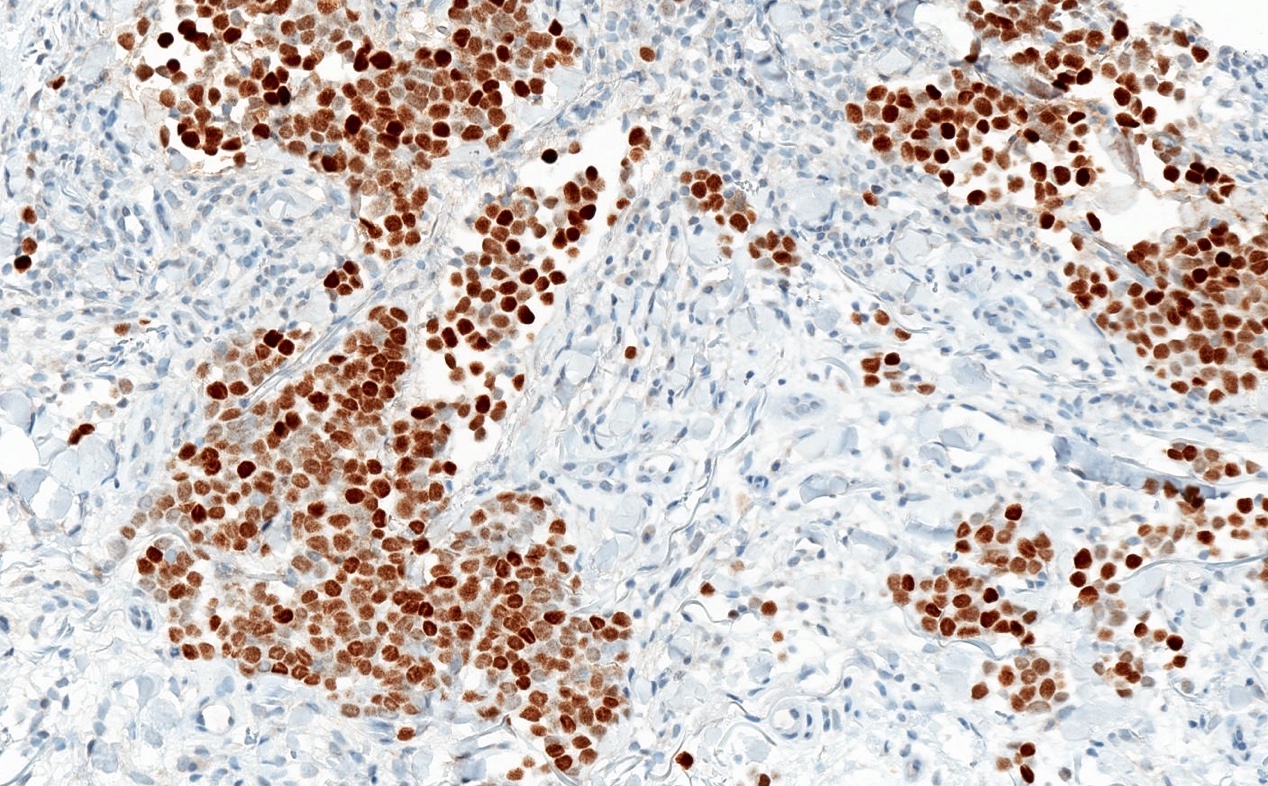

Positive stains

- Broad spectrum keratins: CAM 5.2, AE1 / AE3 (paranuclear, cytoplasmic or mixed pattern)

- CK20 (classic dot-like paranuclear pattern)

- Chromogranin, synaptophysin, CD56, neuron specific enolase

- Neurofilament (dot-like pattern)

- Variable MCPyV (nuclear pattern)

- Can express PAX5, TdT, BCL2, CD99, FLI1